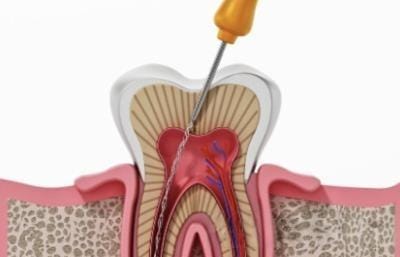

Root Canal Treatment

Root canal therapy saves infected or damaged teeth by treating the inner pulp while preserving the natural tooth structure. With modern techniques, the procedure is comfortable, effective, and long-lasting.